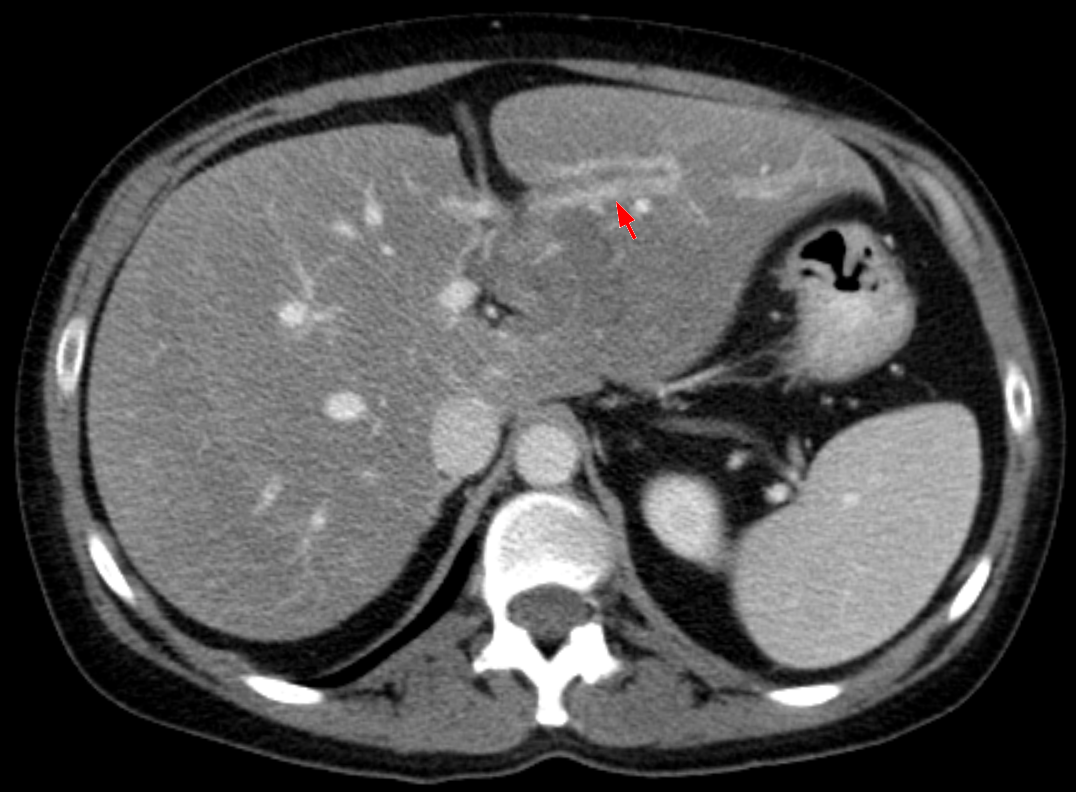

У меня камни в желчном пузыре. Можно ли избавиться от них без операции, раздробить?

Желчекаменная болезнь – одно из самых распространенных заболеваний в мире: каждый 10-й мужчина и каждая 4-я женщина страдает ЖКБ. Главные причины развития данного заболевания – неправильное питание и малоподвижный образ жизни, гормональные нарушения, воспалительные заболевания желчного пузыря.